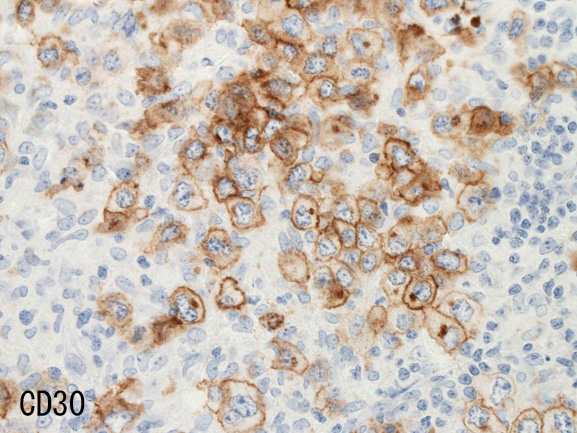

• CD30は50%に陽性。CD15は陰性。

腫瘍細胞はCD20+, CD30+, CD15-, PAX-5+, Oct.2+, BOB.1+(Oct2, BOB1は田丸先生の染色結果), EBER-ISH+, EBNA2-

背景細胞はCD3+ Tリンパ球(CD8>CD4)とCD163, CD68陽性組織球。